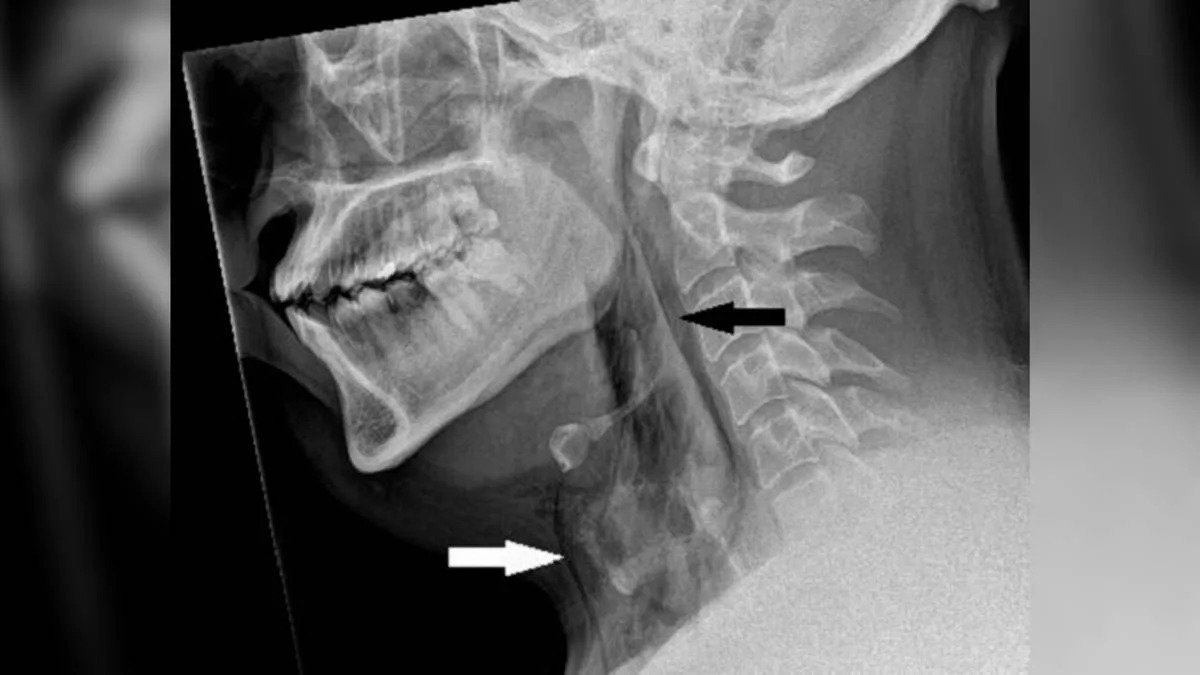

تصویربرداری اشعه ایکس از گردن بیمار نشان داد حباب‌هایی از هوا زیر پوست گردنش گیر کرده است.

تصویربرداری اشعه ایکس از ناحیه گردن بیمار نشان داد وی دچار آمفیزم زیرپوستی شده است. آمفیزم زیرپوستی وضعیتی است که در آن هوا زیر عمیق‌ترین لایه‌های بافتی زیر پوست گیر می‌کند. سی‌تی‌اسکن توموگرافی کامپیوتری نشان داد پارگی بین استخوان سوم و چهارم یا مهره های گردن او رخ داده است. هوا نیز در فضای بین ریه‌های او جمع شده بود. نتیجه‌گیری پزشکان این بود که پارگی درنتیجه‌ی افزایش سریع فشار در نای او هنگام عطسه کردن با بینی و دهان اتفاق افتاده است.